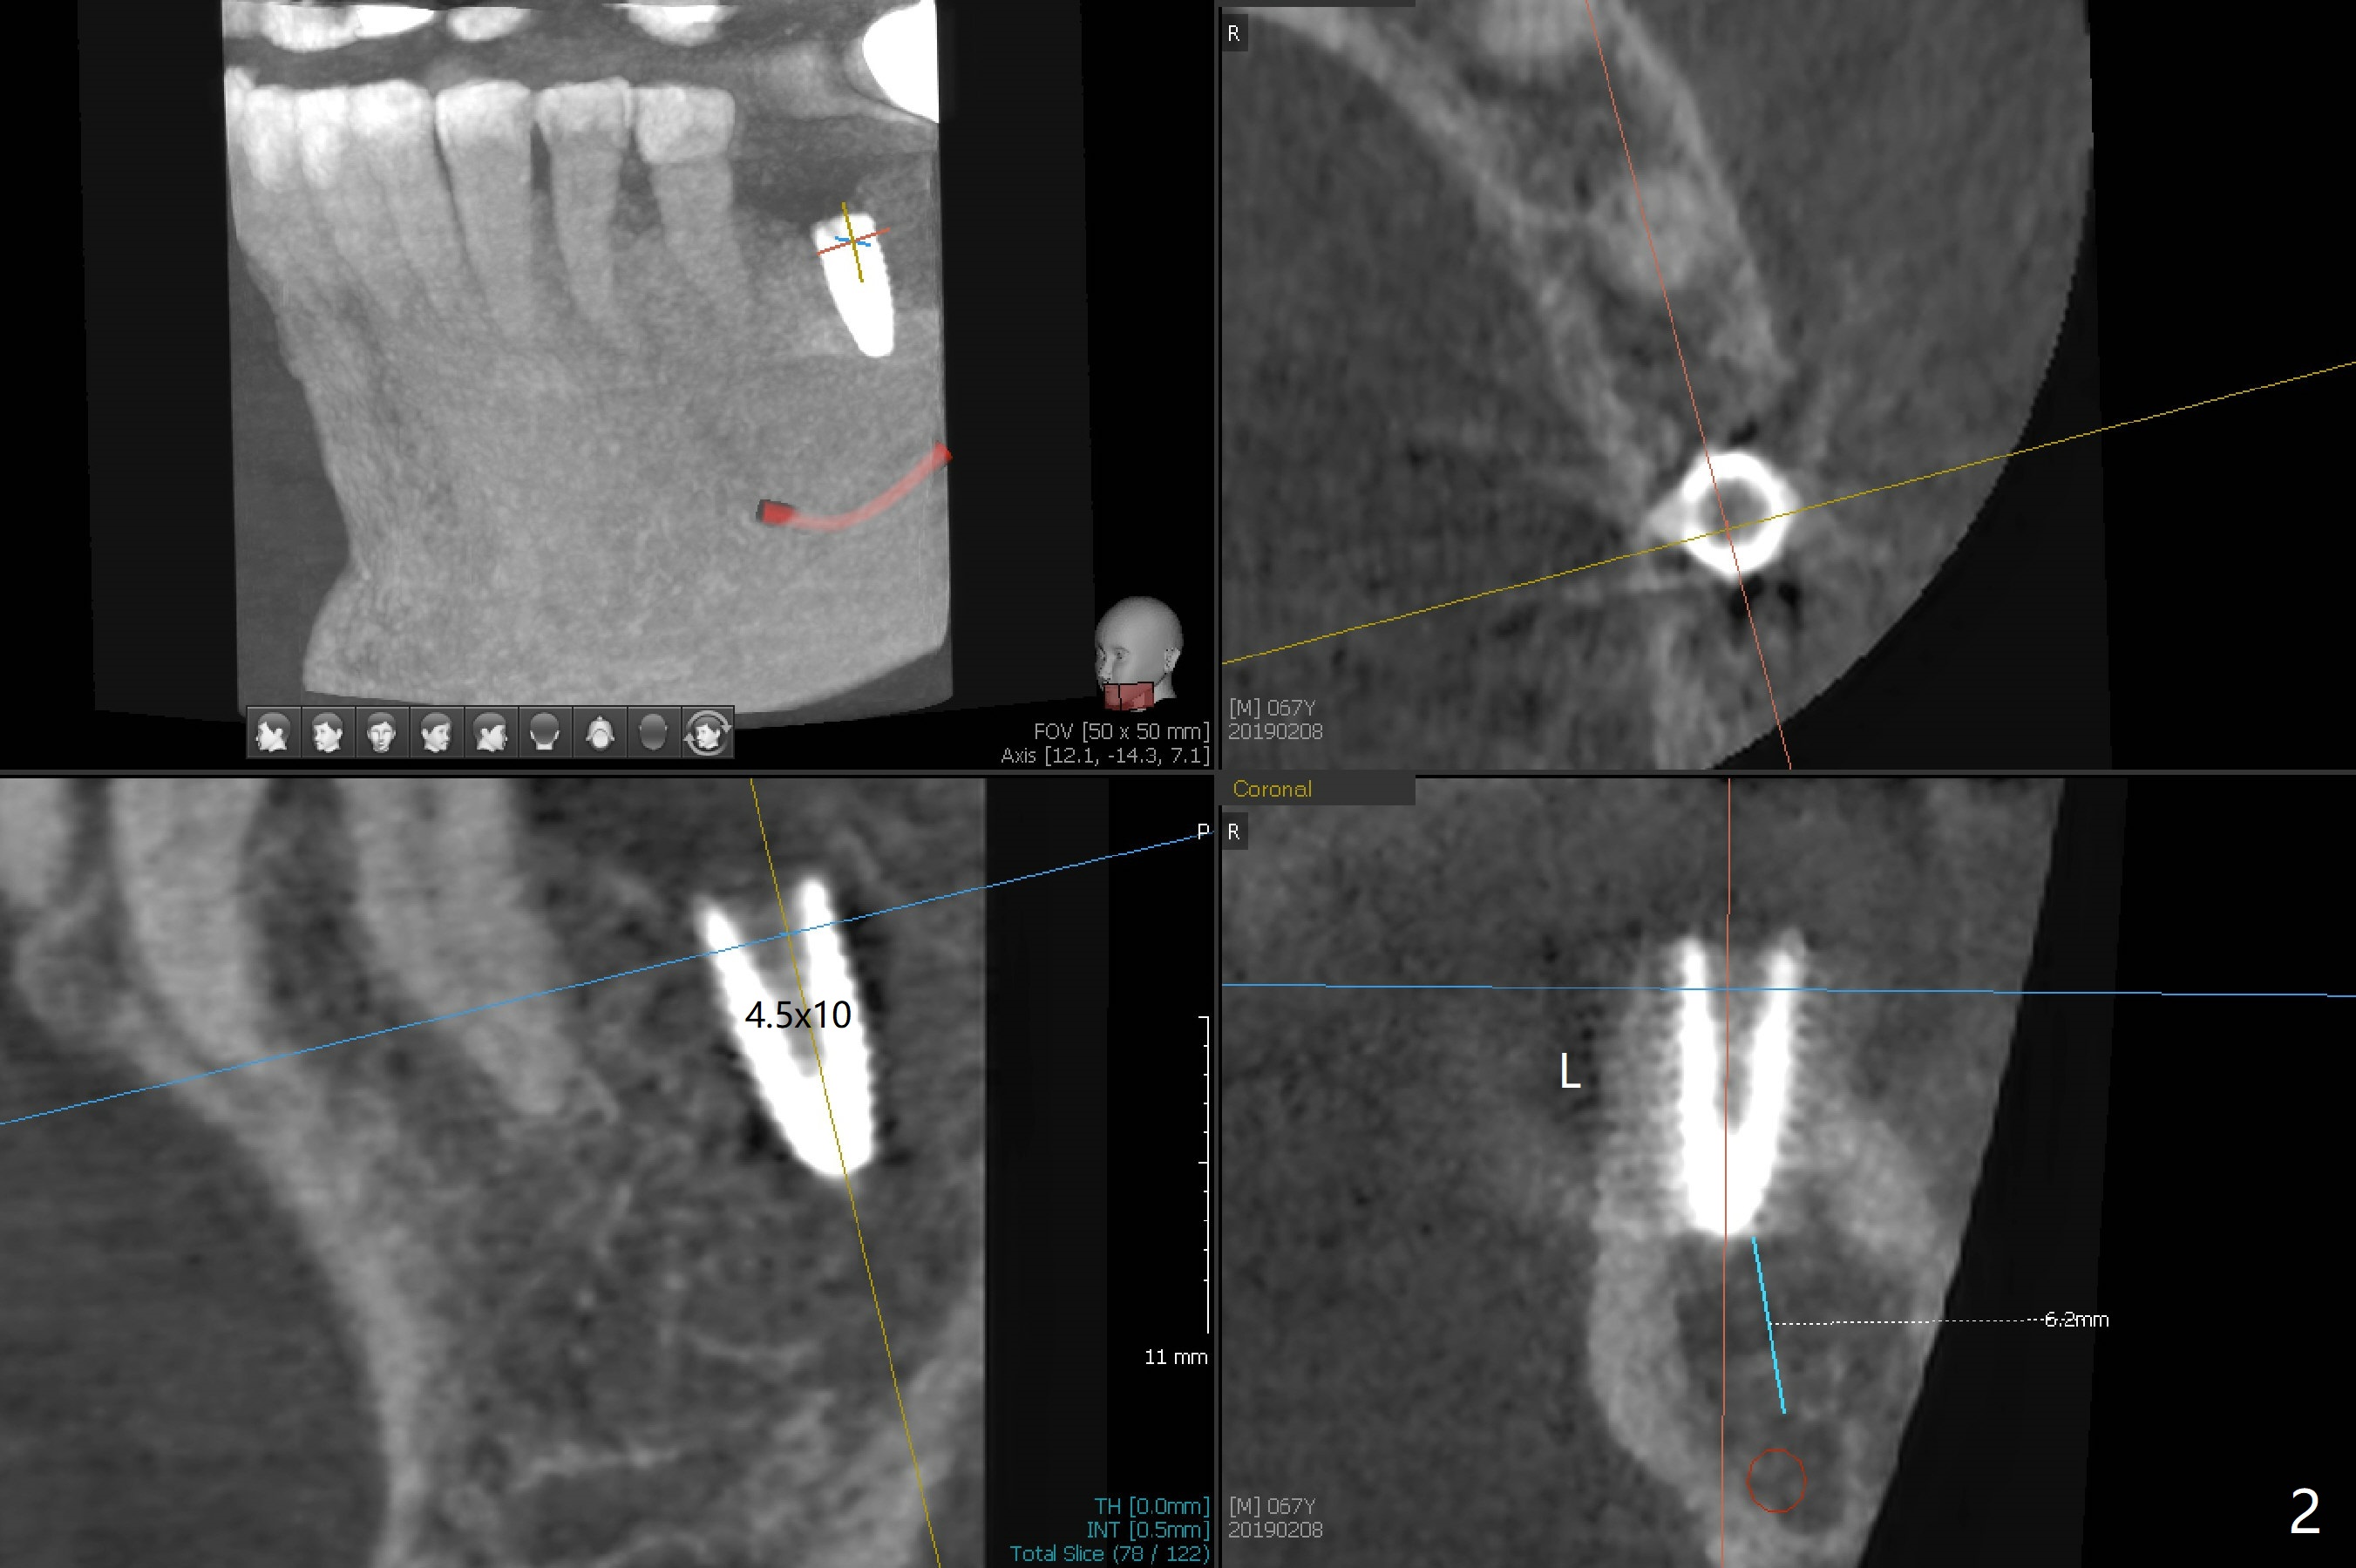

Plate Defect M

Probably due to severe infection at #19, pain control is difficult. Osteotomy has to be stopped 1.5 mm short of the design. PA taken with a 4.5x10 mm dummy implant does not show the Inferior Alveolar Canal (Fig.1), whereas CT does (Fig.2). With 6 mm clearance, block anesthesia is administered. A 5x10 mm definitive implant is placed with ease (Fig.3). The buccal bony defect is repaired by allograft (Fig.3,4 *), while the soft one by 3 pieces of PRF membrane (Fig.5). The latter is fixed in place by applying setting acrylic as an immediate provisional (Fig.6 P) over the wound, around the abutment (A) and locking into the undercut of the neighboring tooth/implant crown. The patient feels great postop. The gingiva is healthy around the provisional 8 days postop (Fig.7). The patient remains asymptomatic with the healthier gingiva surrounding the simplified provisional 22 days postop, as compared to 8 days postop (Fig.8). The socket heals when the simplified provisional is removed 1.5 months postop (Fig.9-12). The bone graft (Fig.11 ^) seems to have become a part of the regenerated gingiva. The abutment has been dislodged for 2 week (Fig.14 (3 months postop). The bone graft, albeit decreased, is 2 mm subgingival (red dashed line). There is bone distal to the implant 11 months postop (Fig.15 *). There is no bone loss 2 years postop; the UF abutment is completely seated (Fig.16).